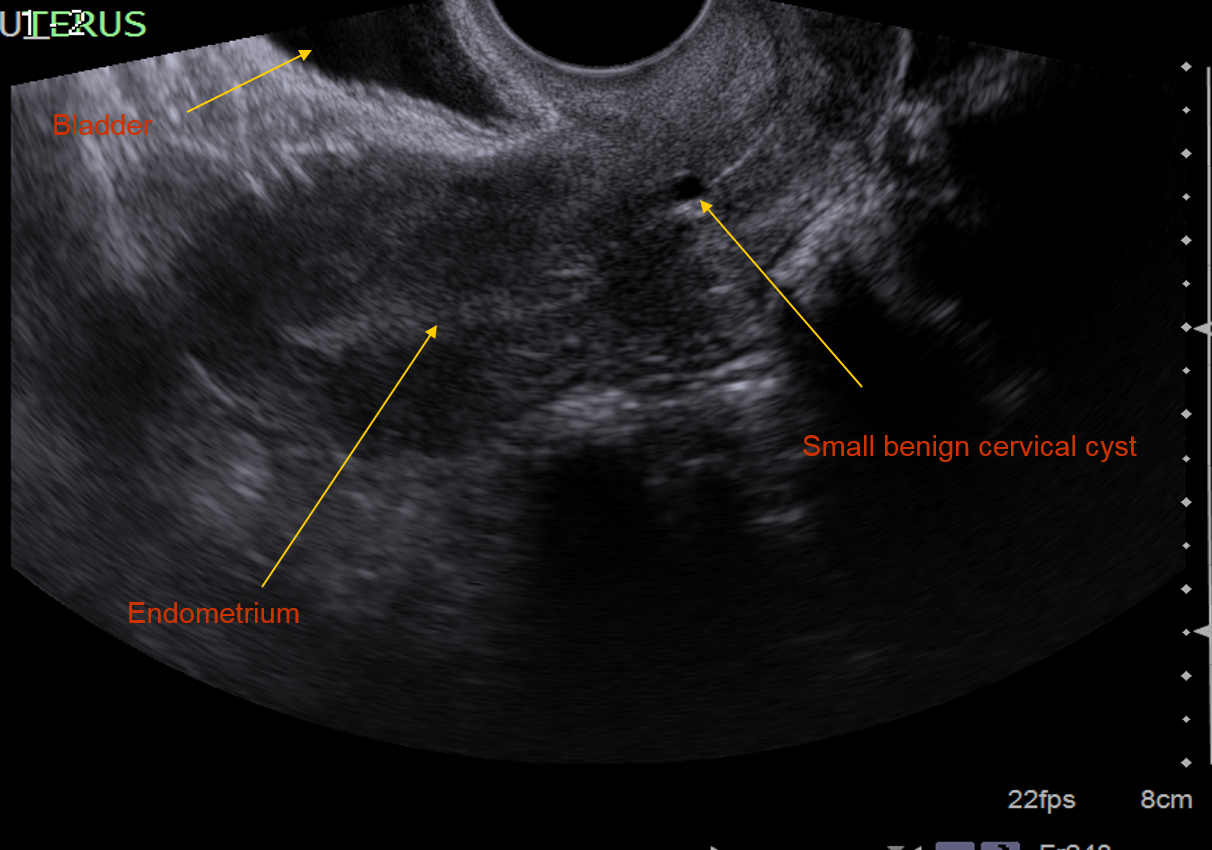

Go over the strctures shown in this transvaginal US

What structure is being shown here? (obtained via TVS)

Ovary